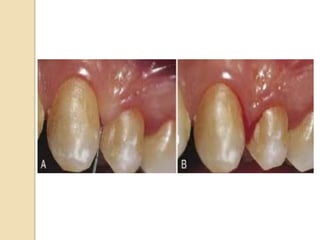

 The insertion of probe to the bottom of the

pocket elicits bleeding if the gingiva is

inflamed & the pocket epithelium is atrophic

or ulcerated.

 To test for bleeding, the probe is carefully

introduced to the bottom of the pocket &

gently moved laterally along the pocket wall.

 Sometimes bleeding appears immediately

after removal of the probe; other times it

may be delayed for a few seconds.

 Therefore rechecking for bleeding 30 to 60

seconds after probing.